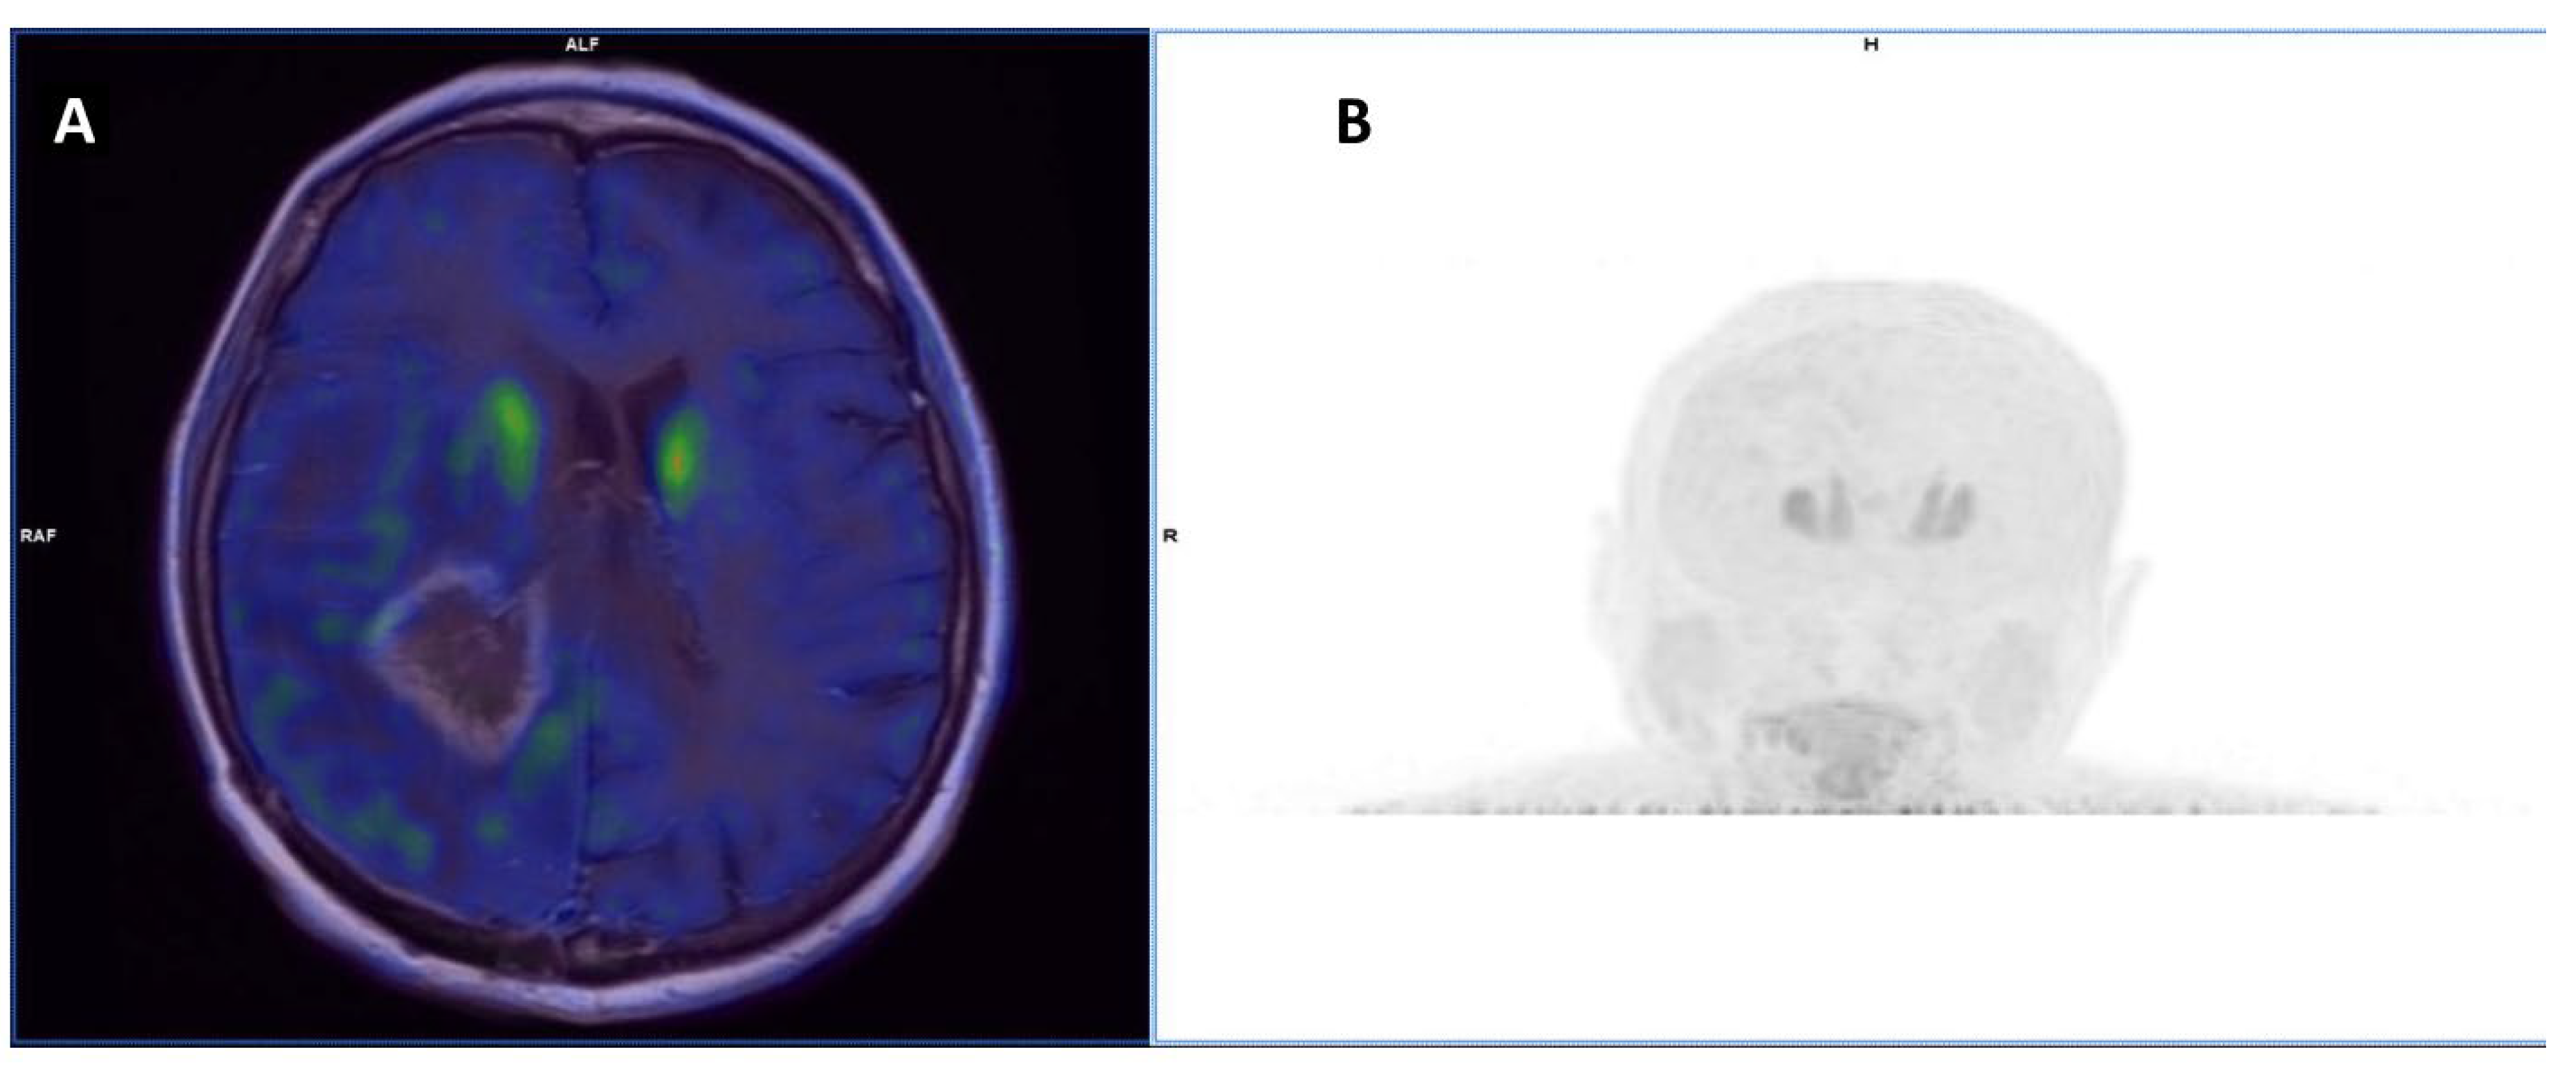

- Øen, S.K.; Johannessen, K.; Pedersen, L.K.; Berntsen, E.M.; Totland, J.A.; Johansen, H.; Bogsrud, T.V.; Solheim, T.S.; Karlberg, A.; Eikenes, L. Diagnostic Value of 18 F-FACBC PET/MRI in Brain Metastases. Clin. Nucl. Med. 2022, 47, 1030–1039. [Google Scholar]

| Øen et al. [62] | 2022 | R | [18F]-fluciclovine | Solid neoplasms | 18 (11/7) | To compare diagnostic accuracy for tumor recurrence between PET/MRI and MRI alone | PET volumes correlated and were comparable in size with those from MRI, but were only partially congruent |